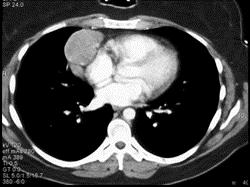

问题 女,27岁,双侧颈部淋巴结肿大,PPD(-),请结合CT图像,选择最可能的诊断 ( )

选项 A.心包囊肿 B.淋巴瘤 C.淋巴结核 D.转移性淋巴结肿大 E.结节病

答案 B